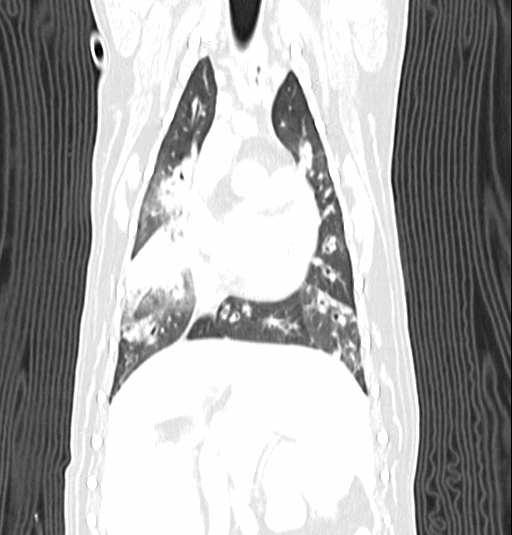

폐 실질 평가, 폐 염전, 폐 종양, 종격동 종양, 심장종양, 폐 전이 평가, 기관, 기관지, 식도의 평가, 복막심낭횡격막탈장, 동맥관개존증